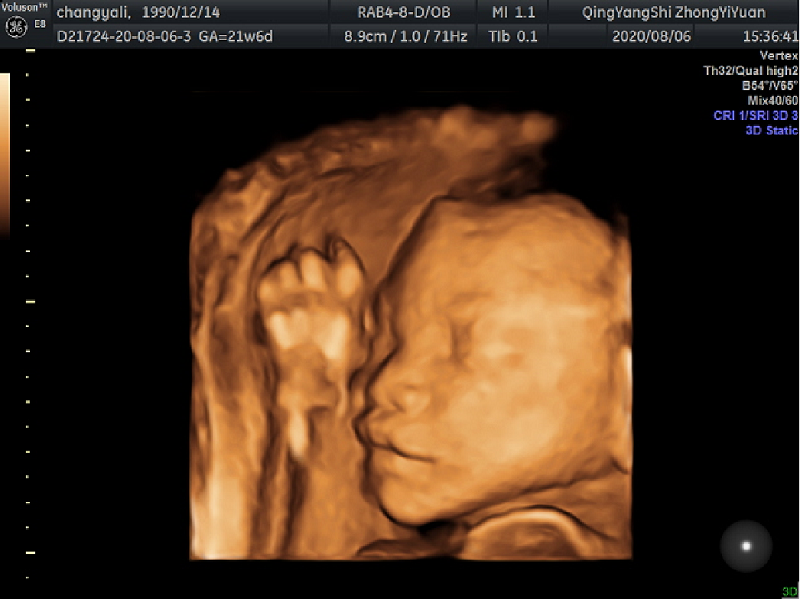

很多孕媽媽在進行孕期的檢查時都需要做胎兒系統(tǒng)性超聲篩查(胎兒四維),那么篩查什么時間做最適合?主要是查什么?到慶陽市中醫(yī)醫(yī)院來做檢查又要注意些什么呢?帶著諸多問題,我們一起去了解一下。

答:胎兒四維即胎兒系統(tǒng)性超聲篩查,主要對胎兒顱腦、顏面部、胸腹部、心臟、四肢等器官系統(tǒng)的大體形態(tài)結(jié)構(gòu)進行篩查,通過數(shù)十個標(biāo)準(zhǔn)切面來評估胎兒結(jié)構(gòu)是否正常。

答:通常在孕22~24周進行,這期間胎兒的基本結(jié)構(gòu)已經(jīng)形成,胎兒大小和羊水量適中,在子宮內(nèi)活動空間較大,形成的圖像比較清晰,有利于醫(yī)生查看。當(dāng)然,每位孕婦的身體狀況不同,做四維彩超的時間也會略有差異,建議做之前咨詢醫(yī)生,謹(jǐn)遵醫(yī)囑。